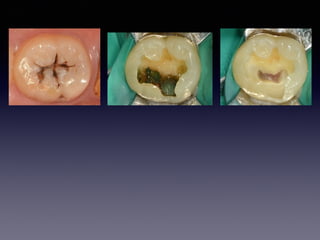

#30 Partial pulpotomy

follow-up case

(23 female)

2013 01 26

2012 10 13

23m later

26

21m later